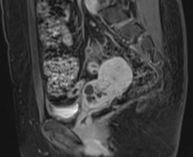

轴位

T2加权像

双侧卵巢增大,间质体积明显增多,T2加权像呈弥漫性低信号,可见多个小卵泡。

右侧卵巢体积为27 cm³。

左侧卵巢体积为26 cm³,内含一个直径15 mm的囊肿,边缘呈锯齿状,周边强化。

未见可疑实性成分或异常增强。

MRI通常显示双侧对称性卵巢增大、均匀T2低信号和轻度间质强化。可见外周卵泡,但数量少于多囊卵巢综合征(PCOS)患者。这些发现与卵巢间质肥大和黄素化卵泡膜细胞相符,这些特征符合卵巢卵泡膜增生症的诊断。